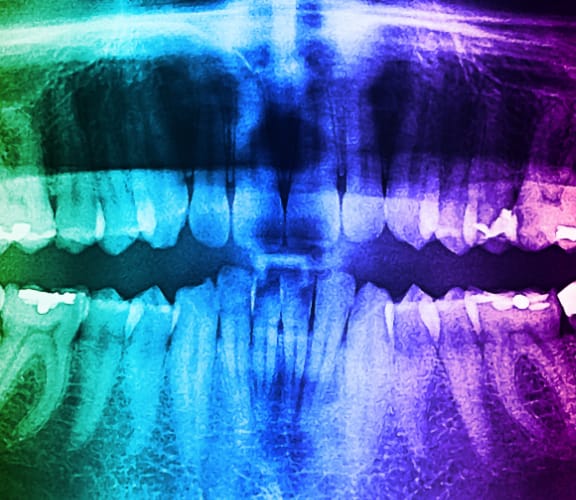

As with any trauma to the mouth, you should consult with us immediately to determine if treatment is required. We will examine the area and take necessary x-rays.

If there is no pain and the chip is small, it's up to you to decide if, when, or how the tooth should be repaired. Depending on the size of the chip, it can be smoothed or cosmetically corrected. Ask us to explain the options available to you. If a filling or artificial tooth becomes chipped, it should be replaced. Cracked or broken teeth should be repaired as soon as possible to prevent further damage. Keep in mind that cracks are not always visible, even on x-rays. Symptoms may involve pain while chewing and sensitivity to cold and/or hot foods as well as liquid or even air, which may over time, become more pronounced.